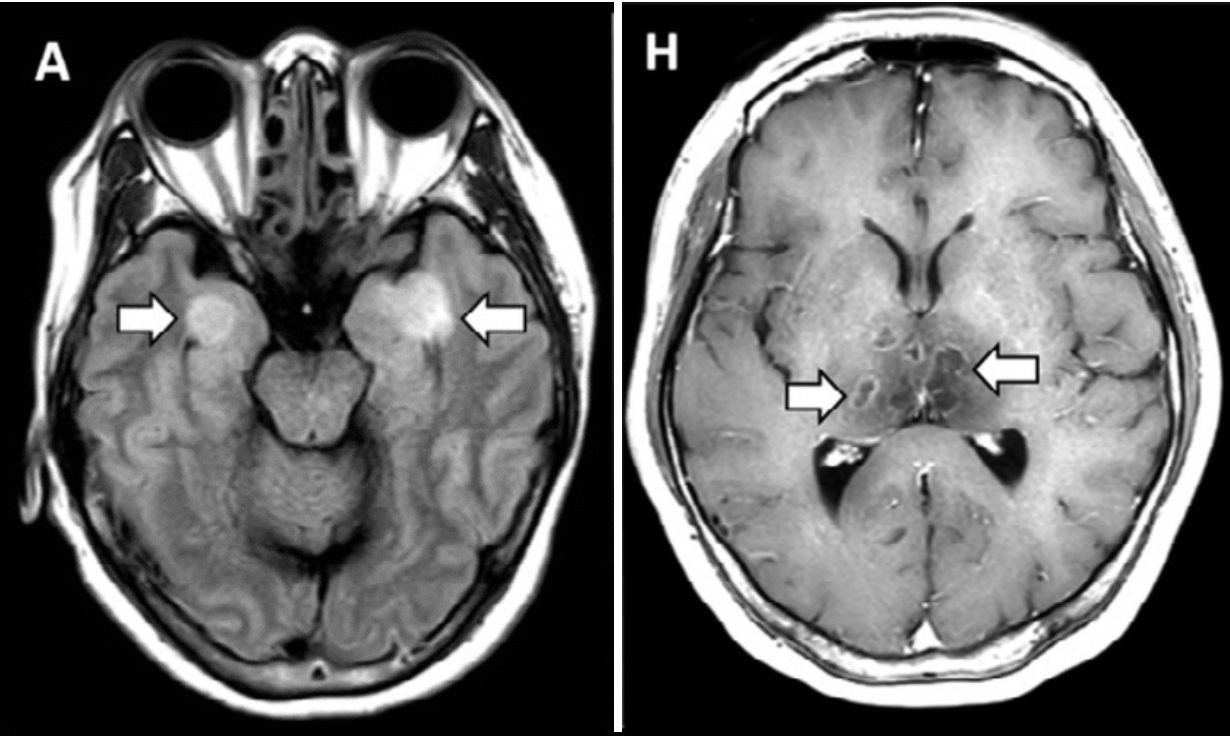

COVID-19–associated Acute Hemorrhagic Necrotizing Encephalopathy: CT and MRI Features. (Poyiadji, et al., 2020)

- First presumptive case of COVID-19-associated acute necrotizing hemorrhagic encephalopathy, a rare encephalopathy that has been associated with other viral infections but has yet to be demonstrated as a result of COVID-19 infection